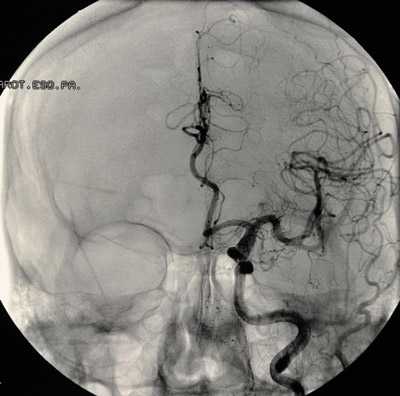

аневризма сосудов мозга на снимке

Перед планированием операции больной подвергается всевозможным обследованиям, включая анализы крови, мочи, коагулограмму, кардиограмму и т. д., как и при других оперативных вмешательствах. Для локализации и уточнения характера сосудистого образования проводят КТ, МРТ с контрастированием, ангиографию, ультразвуковое исследование с допплером.

- цифровой субтракционной ангиографии головного мозга;

- ультразвуковой транскраниальной допплерографии сосудов головного мозга;

- компьютерной томографии (КТ) или магнитно-резонансной томографии (МРТ) головного мозга и его сосудов.